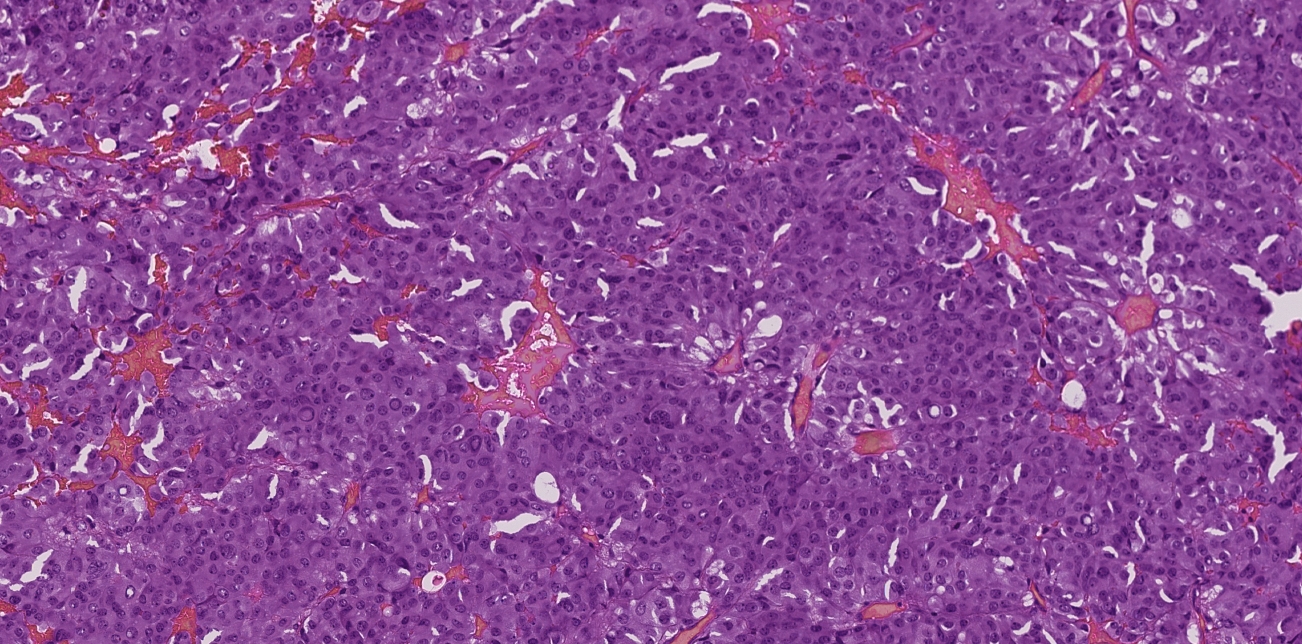

Диагноз тиреотропиномы подтвержден при гистологическом и иммуногистохимическом исследовании послеоперационного материала: экспрессия ТТГ выявлена у 80% опухолевых клеток, индекс метки Ki-67 равен 1,2% (рис. 2).

Рис. 2. а – гистологическое исследование послеоперационного материала: аденома гипофиза из хромофобных клеток (окраска гематоксилином и эозином, ×100); б – иммуногистохимическое исследование с антителами к ТТГ: экспрессия опухолевых клеток до 80% (×100); в – иммуногистохимическое исследование с антителами к Ki-67 (индекс пролиферативной активности): индекс метки Ki-67 равен 1,2% (×200).